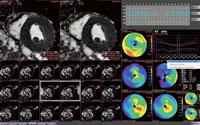

MR遅延造影解析

遅延造影撮像のデータから,心筋梗塞領域の位置と範囲を表示し,Bull’s eye mapで局所の心筋バイアビリティを評価することができる。ワンクリックで外膜側,内膜側をオートトレースする。遅延領域の面積と体積を自動計測し,全心筋,内膜側,外膜側のBull’s eye mapが表示される。

MR心機能解析(RV)(W.I.P.)

今回新たに左室(LV)に加えて,右室(RV)の解析も可能にした。PhyZiodynamicsの技術を応用した心筋の壁の自動抽出が搭載されており,自動補間機能により,ワンクリックですべてのスライスに反映するオートトレース機能を搭載している。

MRストレイン解析(W.I.P.)

MR心機能解析の検査で,心臓にタグをつけてその動きを観察する“タギング”の解析機能を紹介した。PhyZiodynamicsの技術を応用したもので,最新の3T MRIにも対応している。高画質化とともに,タギング機能の組み合わせにより,新しい知見が期待されている。